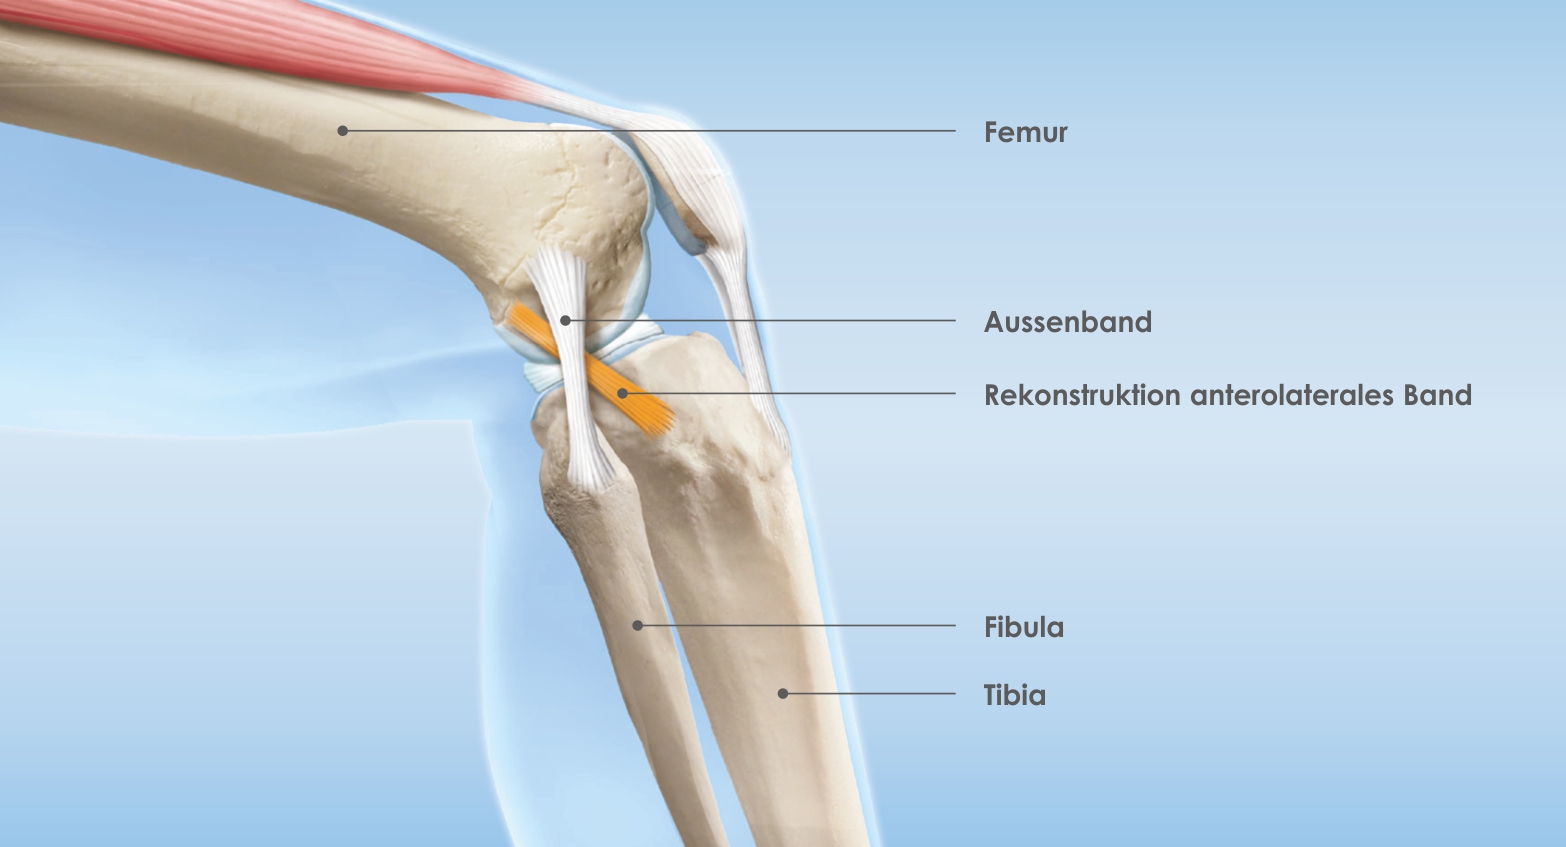

Gelegentlich wird zusätzlich über einen Schnitt an der Aussenseite des Knies das anterolatera le Band (ALL) rekonstruiert, um eine bessere Rotationsstabilität zu erhalten. Auch diesen Aspekt werde ich gerne mit Ihnen besprechen.